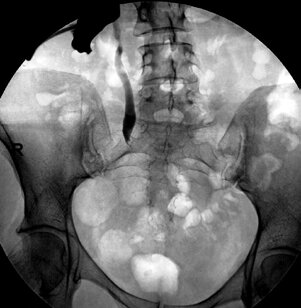

С целью декомпрессии верхних мочевыводящих путей и оценки функционального состояния почки первым этапом была выполнена перкутанная нефростомия справа. При антеградной пиелографии определялась протяженная стриктура тазового отдела правого мочеточника, который контрастировался до средней трети, контраст в мочевой пузырь не поступал (рис. 1).

Рис. 1. Антеградная пиелоуретерограмма справа больной В., 41 год. Протяженная стриктура нижней трети правого мочеточника